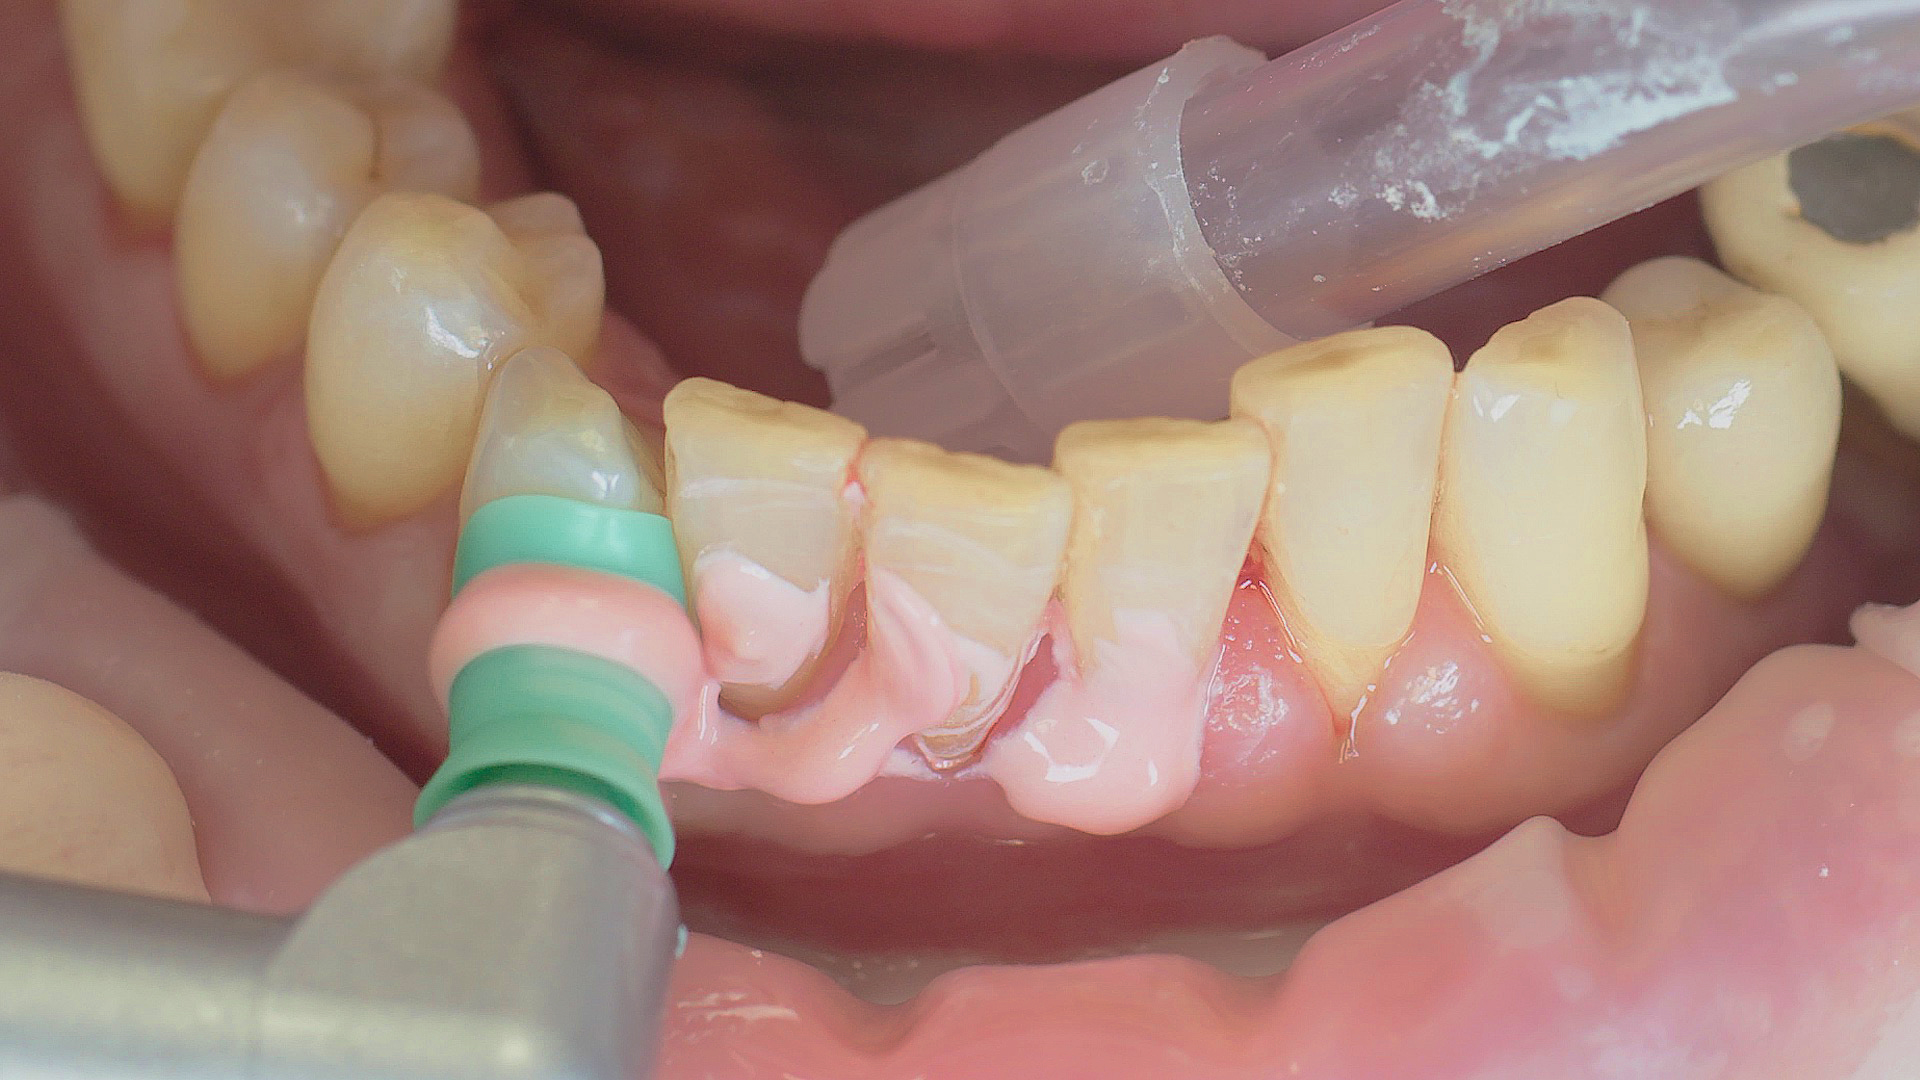

In the periodontal aftercare subsequent to implantation, soft (biofilm) and hard coatings are regularly professionally and mechanically removed.[16, 17] In the subgingival and supragingival areas, ultrasonic devices are generally used for this (Fig. 4), in combination with manual instruments where necessary. Alternatively, subgingival air polishing can be used in combination with periodontal attachments and powders.[18]

Ultrasound devices are particularly suitable for UPT

Fig. 4: Ultrasound devices are particularly suitable for UPT, for example in combination with periodontal tips (W&H Tigon+ with 1P tip)